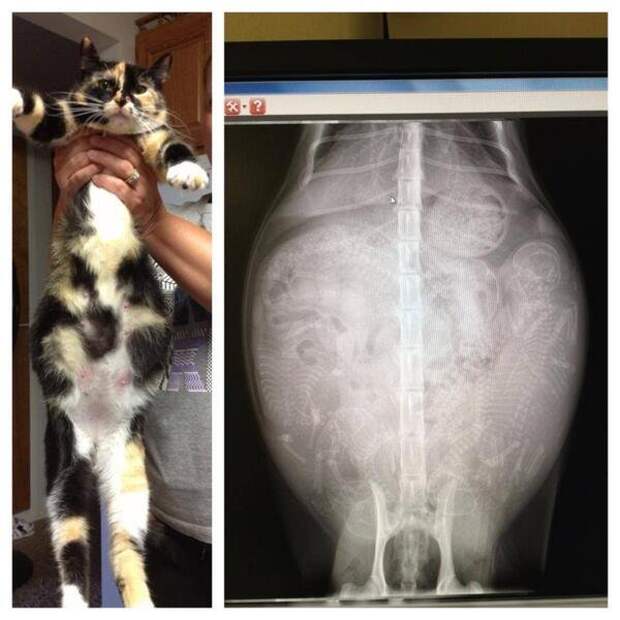

Беременная кошка.

Еще одна беременная кошка.